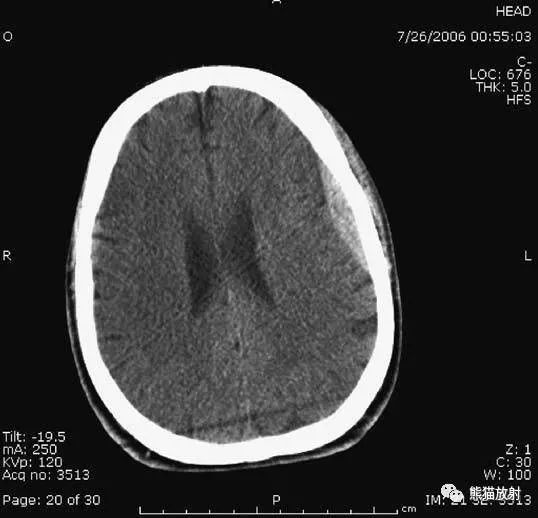

颅脑CT常用的三个窗(图A-C):图A:骨窗(the bone window)。

图B:脑窗(the brain window)。

图C:血窗(the blood window)。

图A:骨窗;主要用于明确骨折、窦腔病变、颅内积气。

图B:脑窗;可清晰显示灰白质,可发现中风的早期征象或其他导致脑水肿等表现的病变。

图C:血窗;更利于显示硬膜下或颅内出血。本例表现:骨窗示:右顶骨骨折;三个窗均示:软组织水肿并皮下积气;血窗:少量硬膜下血肿。